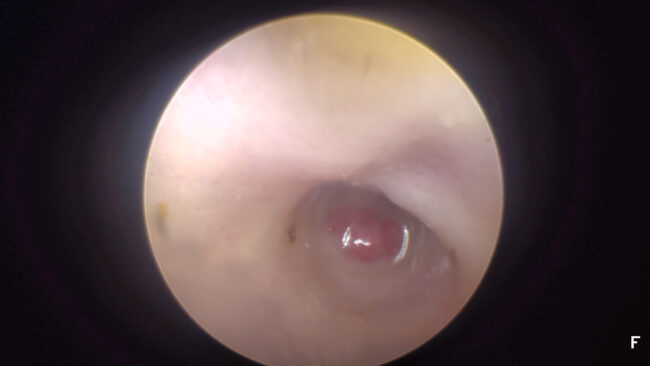

Nous évoquions dans un post précédent la propension des bouledogues français à développer des otites moyennes suppurées, comparés à d’autre races brachycéphales. Une nouvelle étude vient montrer à quel point ce risque doit être pris en considération. Il s’agit de la recension de 10 cas de méningite suppurée otogénique, c’est-à-dire issue de l’oreille moyenne/interne. Ces…